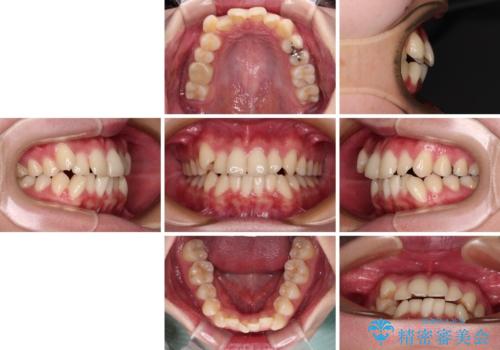

- 患者様

- 30代女性

- 治療期間

- 1年11ヶ月

- 八重歯やクロスバイトを気にして来院された患者様です。

口元の突出感はありませんでしたが、デコボコが強く、非抜歯矯正とすると出っ歯仕上がりとなる可能性があったため、上下左右の第一小臼歯4本を抜歯し、ワイヤー装置にて矯正治療を行うこととしました。

デコボコがスッキリするだけでなく、口元の突出感も少し改善され、満足のいく仕上がりとなりました。